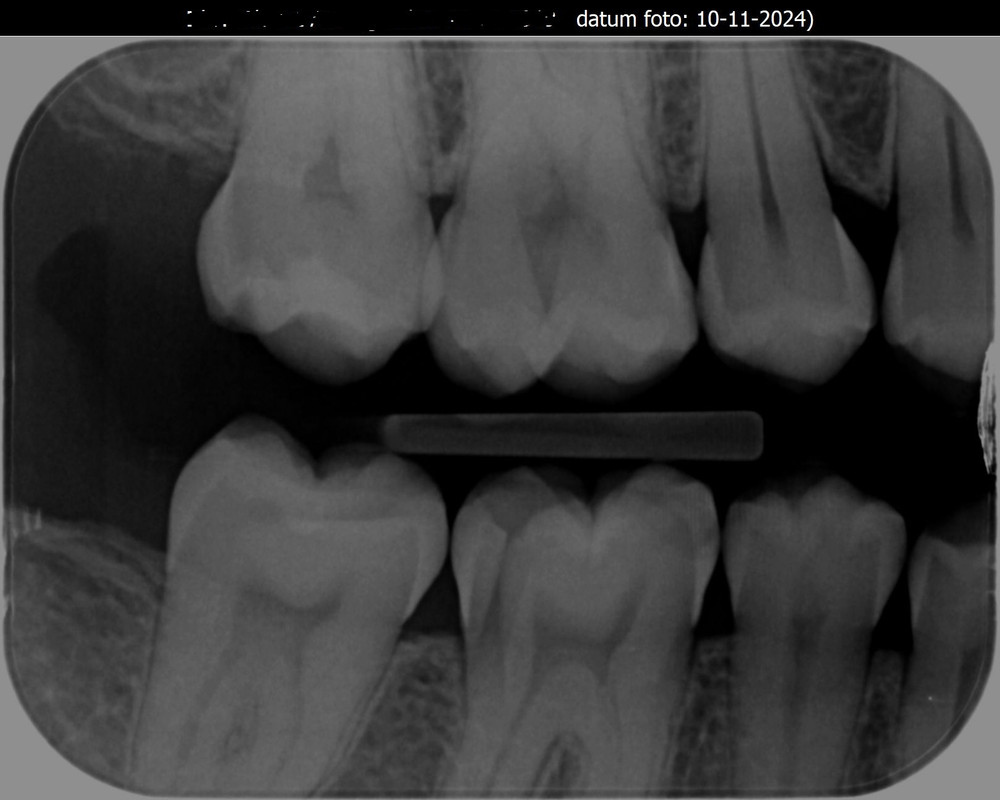

Ik heb de foto bij de tandarts opgevraagd. Wat vinden jullie?[/img]https://i.postimg.cc/8Pg5bcfR/064020-001-20241115.jpg[/img]

[img]https://i.postimg.cc/XvBShKTp/Visi-Quickv12-10-11-2024-1.jpg[/img]

[img]https://i.postimg.cc/XqQzXXTR/Visi-Quickv11-10-11-2024-1.jpg[/img]